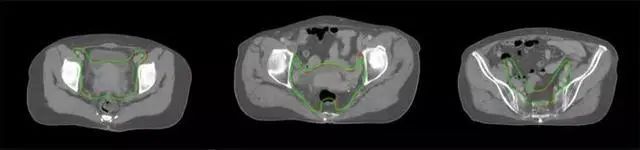

放射治療,簡稱放療,是治療腫瘤主要手段之一,利用放射線破壞照射區(qū)(靶區(qū))的細胞,使腫瘤細胞停止分裂直至死亡,醫(yī)生通常把放射治療形象的比喻為“打靶”,放療前精準勾畫腫瘤靶區(qū)范圍是腫瘤放射治療的關鍵步驟。傳統的靶區(qū)勾畫醫(yī)生會根據患者多張CT、MRI影像片憑借經驗進行,比較耗時,治療的病人數量也有限,且靶區(qū)勾畫缺少行業(yè)統一的規(guī)范和標準,無法達到同質化,勾畫精確度不理想。

技術原理

基于深度學習人工智能的放療靶區(qū)智能勾畫技術和自動計劃技術,基于全面的市場調研和臨床專業(yè)意見,采用獨創(chuàng)的基于小樣本量的人工智能算法,實現放療靶區(qū)和危及器官的快速全自動勾畫。

產品優(yōu)勢

縮短至幾分鐘內便可完成,大幅提升了放療效率,且人工智能平臺完成的靶區(qū)勾畫可基本滿足臨床醫(yī)生需求,專家只需審核時細微調整,可顯著提高靶區(qū)勾畫的規(guī)范化及精準度,讓放療智能化,標準化。可覆蓋食管癌、鼻咽癌、直腸癌、宮頸癌、肺癌等多種病種。